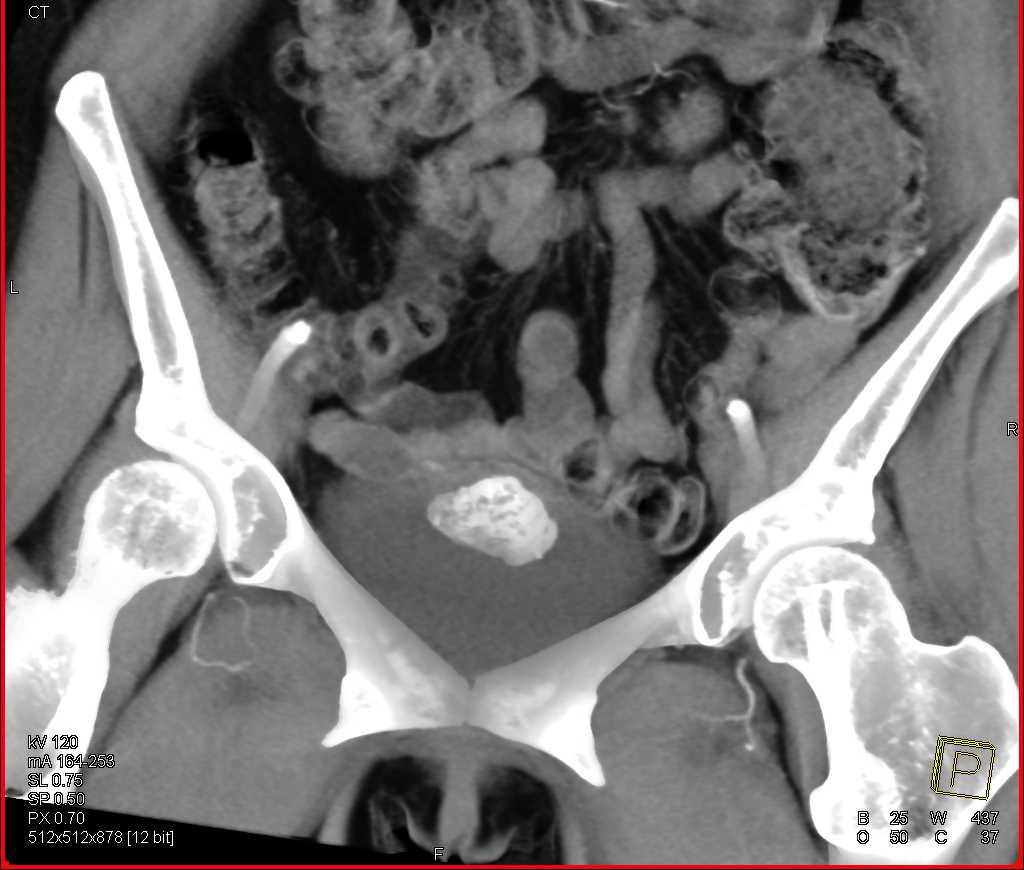

Urachal Carcinoma of the Bladder